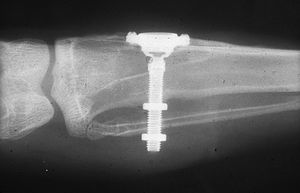

اذا كان العظم على استعداد لتلقي الزرع (أحيانا بعد سلسلة علاجات مسبقة)، يمكن البدء بعملية زرع الاسنان. يتم تثبيت المسامير المعدنية اللولبيه براغي، بعظم الفك. في سلسلة اخرى من العلاجات بعد فترة من ادخال البراغي، تبدا عمليات اعادة البناء عن طريق أخذ القياسات وانشاء التاج/الجسر. عندما يدور الحديث عن فترة الانتظار بين تركيب الغرسات وبين تنفيذ الاستبناء النهائي، فان هنالك اكثر من نهج واحد. النهج المتبع غالبا هو الانتظار لمدة 6 أسابيع على الأقل حتى تلتئم الانسجة، وأحيانا تصل فترة الانتظار لعدة شهور.

وأخذ النوع الرابع شأنه الكبير في الستينات من القرن العشرين، وكان ستروك (1939) أول من قام بغرس لولب في العظم للتعويض عن سن مقلوعة.

في عام 1976 صنع كوخ الغرسة الأسطوانية، وتمتاز بما يلي:

- تحضير الفتحة العظمية سهل إذ يتم بوساطة سنبلة خاصة مما يحقق تماساً جيداً بين الغرسة والعظم.

- يمكن فصل الجزء البارز خارج العظم عن الغرسة بحركة لولبية مما يحقق لمنطقة الغرسة المغلقة تحت الغشاء المخاطي والسمحاق شفاء جيداً.

- يمتص الغشاء المصنوع من اللدائن والمغطي للمهماز الخارجي شدة الصدمة الواقعة على الغرسة في أثناء المضغ.